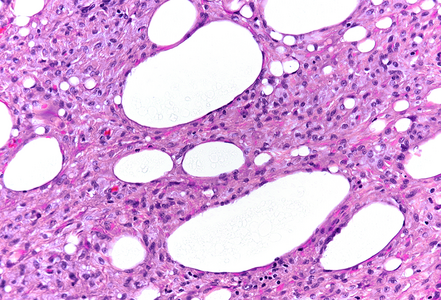

The resection specimen contained superficial remnants of the previously excised tubular adenoma (not shown). Close to the neoplastic glands, however within the submucosa, nodular aggregates of histiocytes were found (Panel A), that included vacuoles of varying size; these vacuoles were mainly empty, except for few tiny droplets of pale fluid or substance (Panels B and C). A CD68 immunostain confirmed histiocytic cell origin (Panel D). Pankeratin staining was negative within the lesion. No atypia was observed, and no eosinophils were present. The histological findings in combination with a history of polypectomy at the same site were consistent with the diagnosis of a “lifting agent granuloma”.